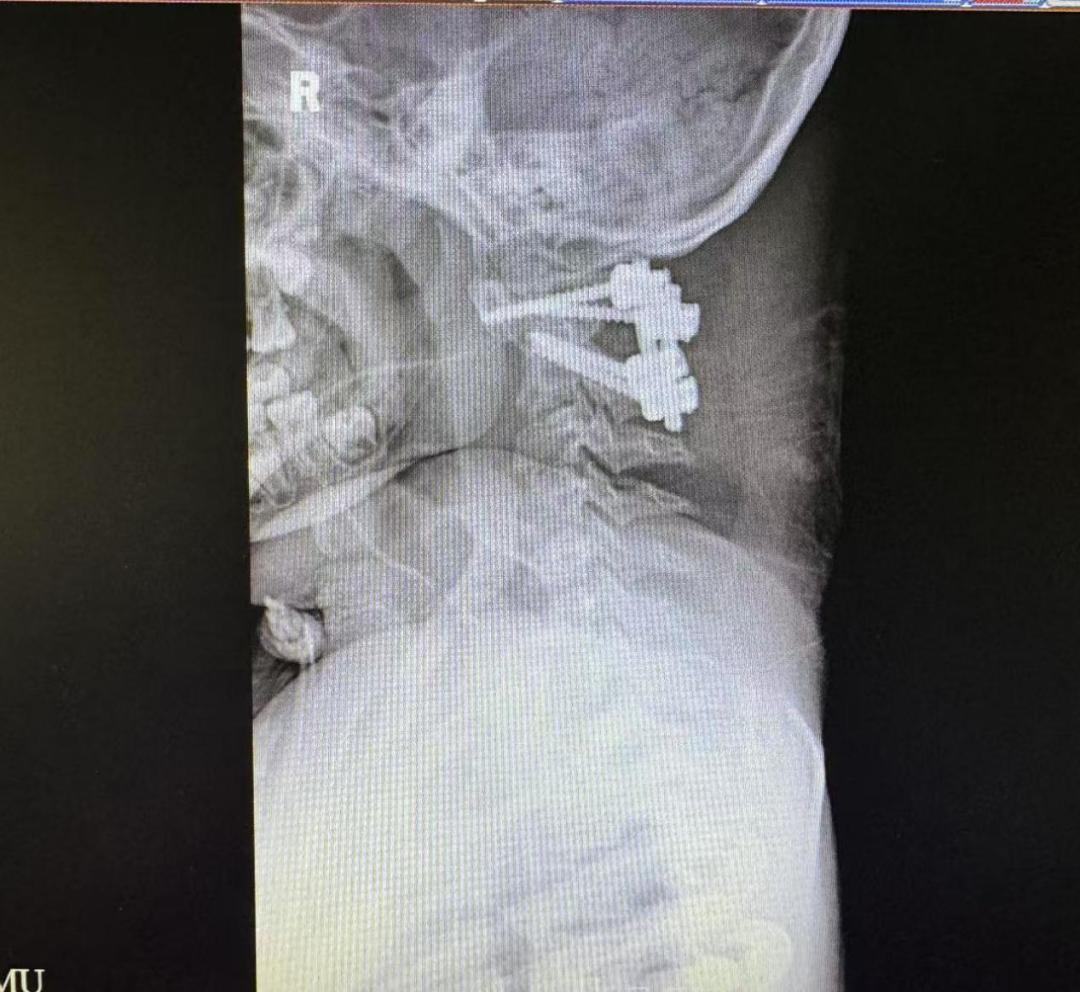

术前术后颈椎X光片

为解决这个问题,脊柱外科一科主任王亮在术前采用3D打印技术复刻了乐乐的寰枢椎模型,反复进行充分的手术模拟。几次模拟下来,王亮有了信心,决定直接实施颈椎后路手术复位手术。术中,团队紧密配合,将手术精度控制在“毫米级”,一次性精准置钉,完成寰枢椎复位与固定。

儿童寰枢椎脱位的致病机制是多种多样的。唐氏综合征的患儿通常由于染色体易位,出现寰枢椎周围韧带松弛,骨骼发育迟缓,齿突小骨结构异常等问题,常常引起明显的寰枢椎关节不稳。虽然儿童寰枢椎脱位手术原则与成人基本一致,但相对于成人,儿童颈椎发育不完全,解剖结构均细小,手术难度非常高。而且目前国内外并未针对儿童患者寰枢椎设计对应的内固定系统,只有成人的内固定装置可供选择。因此针对这类患儿,就更需要足够的术前准备和规划。“得益于术前从影像资料上详细测量的解剖参数,结合3D打印技术,终于做到真正的个体化操作,保障手术的顺利、患者的安全。”